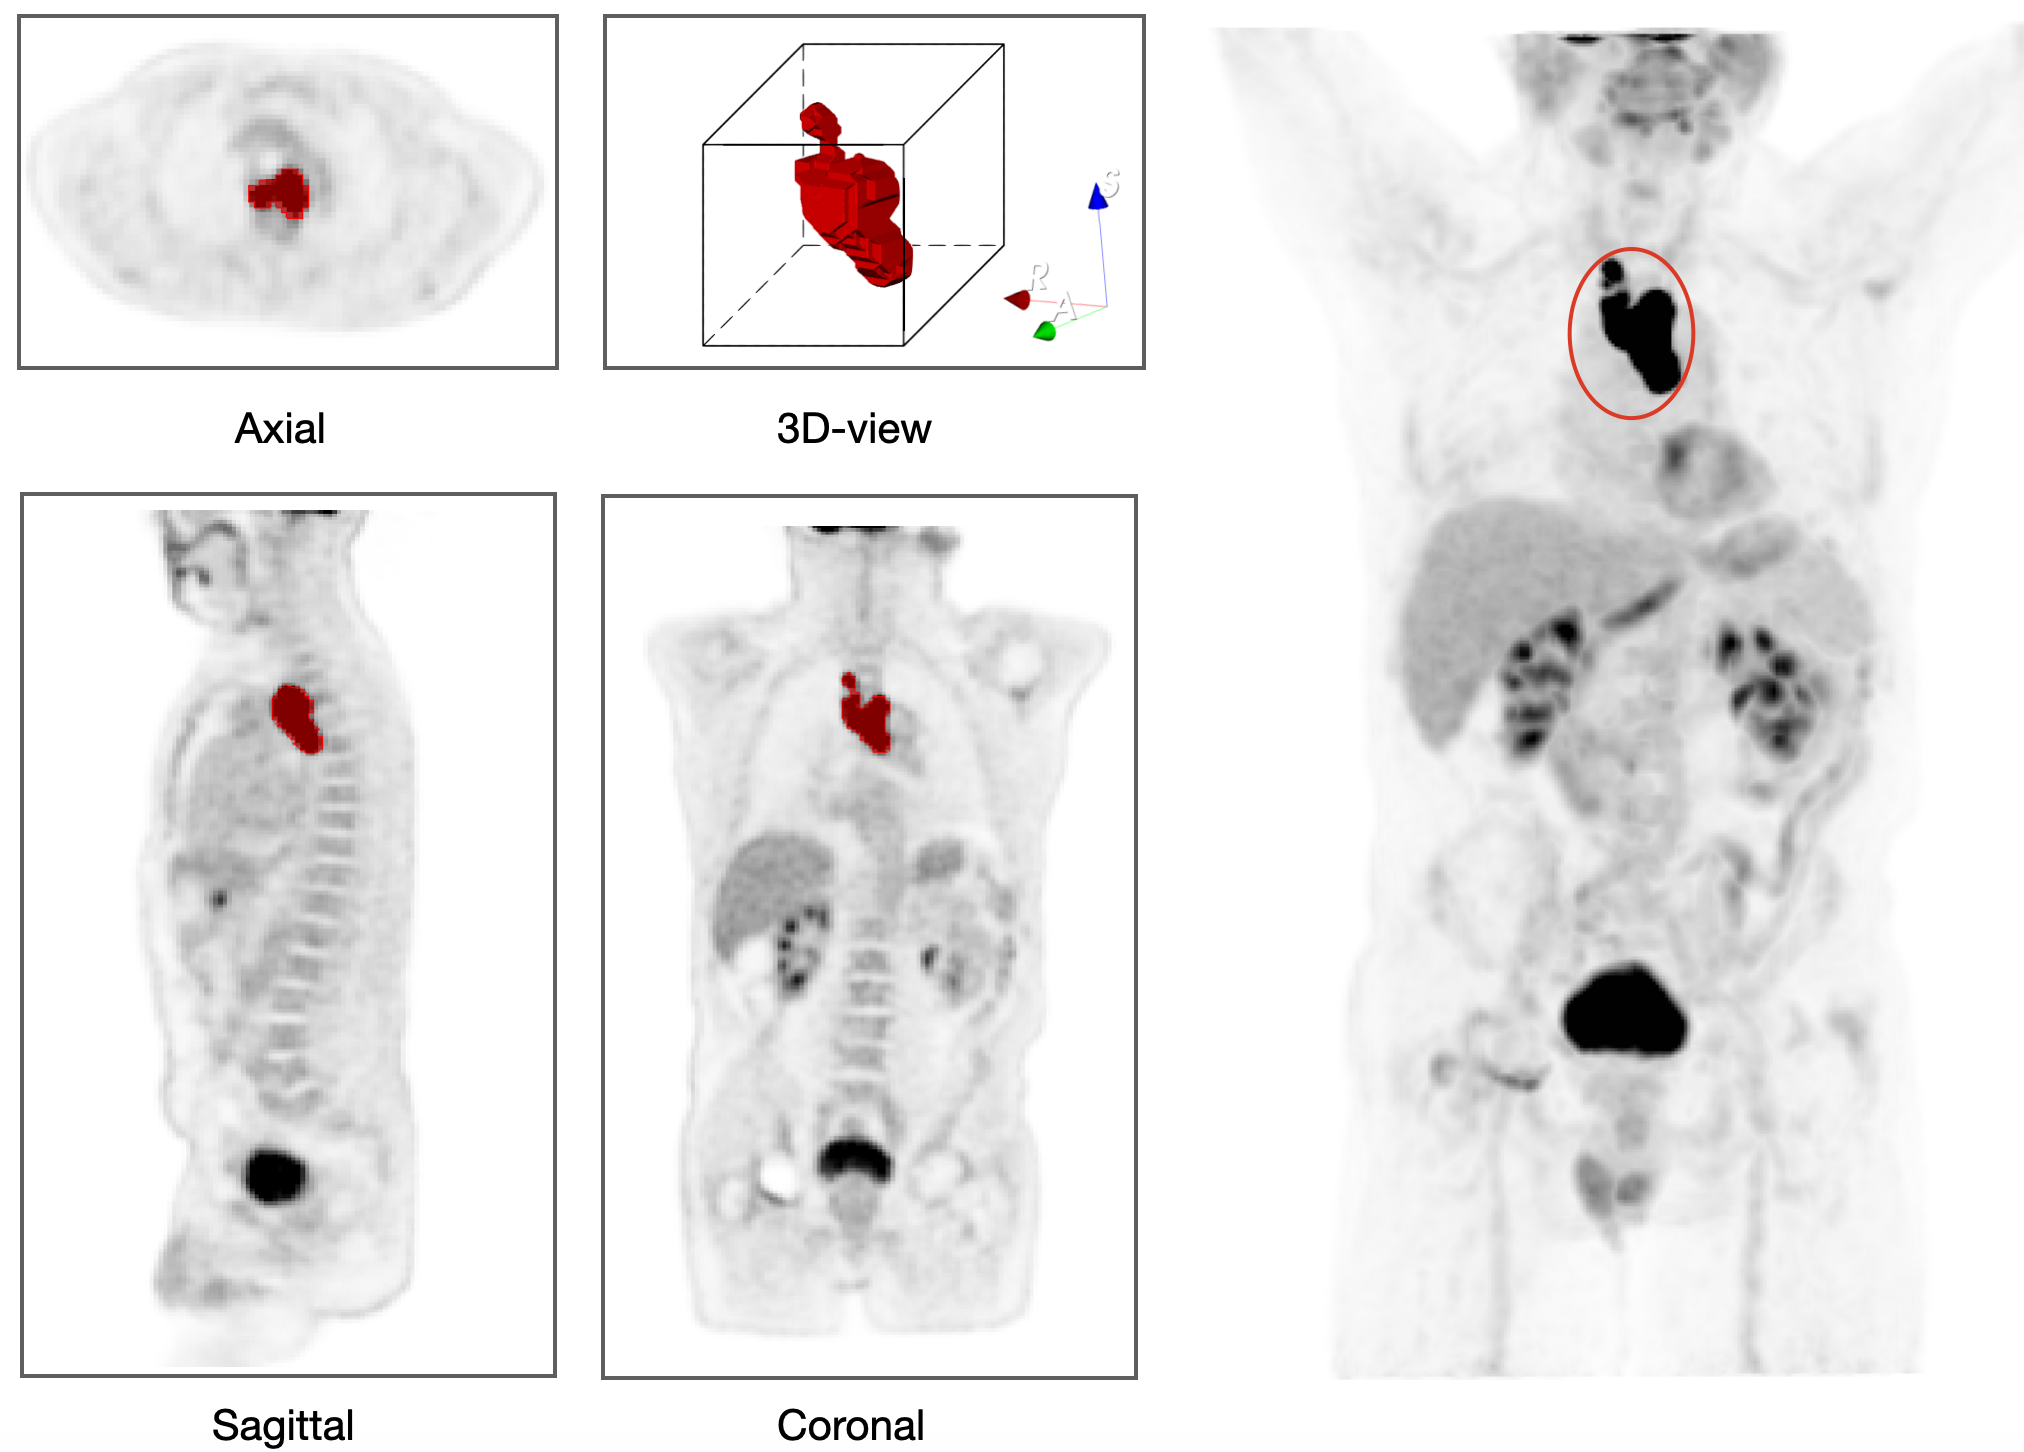

Details of model parameters, as well as their units and values used throughout this study are given in Table 2. We computationally studied the long-term outcome of the treatment by varying the tumor proliferation rate a𝑎aitalic_a and tumor lesion sphericity ΨΨ\Psiroman_Ψ within ranges estimated from literature and our own dataset. Figure 2 shows representative examples of sphericity values observed in 18F-FDG PET images of different lesions from lymphoma patients included in the study. This visualization highlights the morphological heterogeneity among lesions, suggesting that lesion geometry could be a potential factor influencing treatment response and long-term therapy outcome.

Refer to caption

Figure 2: PET/CT images of two different patients showing lesions with varying sphericity values (ΨΨ\Psiroman_Ψ). (a) 3D view of a full-body 18F-FDG PET scan of a lymphoma patient (rightmost image), with the coronal PET scan displaying three lesions of different sphericities, as shown in axial PET slices (leftmost images). (b) 3D view of a full-body PET scan of another lymphoma patient, with the coronal PET scan showing two lesions with different sphericities, along with several axial slices. Higher ΨΨ\Psiroman_Ψ values indicate more spherical lesions, while lower values correspond to irregularly shaped lesions.